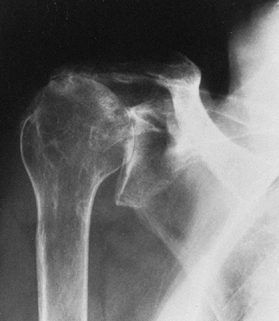

Posttraumatic arthritis in which joint incongruity or malunion has destroyed the glenoid (Fig. 101.11)

Figure 101.11.

Axillary radiograph in patient with posttraumatic arthritis. There is

amount and position of glenoid wear, the extent of medial migration,

and the position of the humeral head (Fig. 101.11, Fig. 101.14).